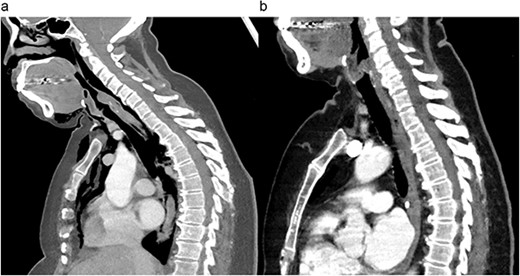

Within 12 hours of discharge, she was readmitted with dysphonia and florid oedema of the head and chest. A CT chest demonstrated a 6 cm laceration of the distal trachea 2 cm above the carina, with diffuse subcutaneous emphysema (Fig. 1a).

Preoperative (a) and postoperative (b) sagittal CT views of the thoracic cavity, demonstrating a large posterior tracheal defect extending to just above the carina, and its resolution postoperatively.